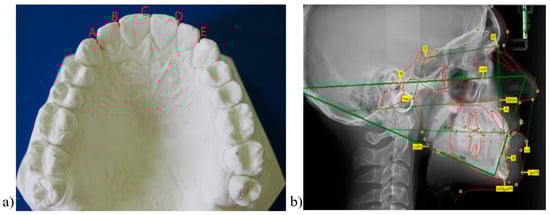

The assessment of the correct teeth positioning at the end of the active orthodontic treatment was made by clinical observation, measuring irregularity index using study models (Figure 1a), and by cephalometric assessment of the inclination of the upper incisors. Thus, we assessed the anterior–posterior position of the upper incisors at the end of the orthodontic treatment by measuring 1—A-Pog (upper central incisor to A-Pog) angle (angle formed by the extension of the longitudinal axis of maxillary incisor to the A-Pog line, with normal values of 3 ± 5 degrees) on the lateral cephalograms. To measure the 1—A-Pog values, we used a computerized defalcation software entitled OnyxCeph version 69 (open software license) (Figure 1b). In order to analyze the correct alignment of the anterior maxillary teeth at the end of the orthodontic active treatment (prior to the application of the removable retainer), but also during the first year of the retention phase in cases with changes in the position of the upper teeth (respectively the cases with relapse), irregularity indexes (similar to the index introduced by Little R.M. [24] for the six anterior mandibular teeth—Little’s irregularity indexes) were measured on dental casts. The irregularity index was calculated based on the linear measurement of displacements in the anatomical contact points of upper anterior teeth, parallel to the occlusal plane (Figure 1a). We used a digital caliper with a 0.01 mm sensitivity for these measurements. All cephalometric analyses and dental cast measurements were performed by the same investigator to avoid inter-operator bias.

Figure 1. (a) Dental cast measurements: Irregularity index (A + B + C + D + E); (b) Cephalometric analysis using OnixCeph software.